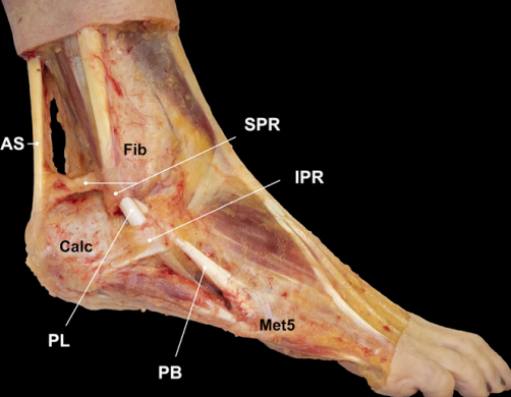

腓骨长短肌位于小腿外侧间隔。

腓骨长肌(PL):起于腓骨头、腓骨外侧面上2/3和小腿深筋膜,止于第1跖骨外侧及毗邻的第1楔骨的内侧,至小腿下1/3处,长肌移行为肌腱,在它到达止点前的行程中有三个弯曲,第一个在外踝顶点,第二个在跟骨外侧壁的腓骨肌滑车下,第三个在骰骨结节处经90°转到足底。

腓骨短肌(PB):起于腓骨外侧面下2/3及前后肌间隔,短肌至外踝的后下方始为移行为肌腱,紧贴于外踝后方,通过外踝顶点转向足外侧前方,经过跟骨外侧壁腓骨肌滑车上方最后止于第五跖骨基底。

腓骨肌腱鞘:起于外踝顶点上3.5cm并向远端延伸4cm,在腓骨的远端,腱鞘分为两部分,腓骨长、短肌腱各自进入独立的滑液鞘。

腓骨外踝窝:外踝的后方近端较宽广,远端呈锥形变小并有一浅的沟。

纤维软骨脊(FCR):腓骨外踝窝的外侧缘有一纤维软骨形成的缘,构成了窝的结构。该纤维软骨脊近端明显,向远端渐变小,使得沟的整体深度增加了2-4mm,且形状更适于容纳腓骨肌腱,从而促进应力分散。

腓骨上支持带(SPR):起于腓骨外侧面和腓骨外踝窝,绕过腓骨肌腱后止于跟骨和跟腱外侧。SPR没有直接牢固固定于纤维软骨脊,而是与腓骨外侧面的骨膜融合。

下支持带(IPR):前上方与伸肌支持带外侧根延续,后下方附着于跟骨前部外侧面。在跟骨滑车上下形成两个纤维管道固定肌腱于跟骨外侧壁。